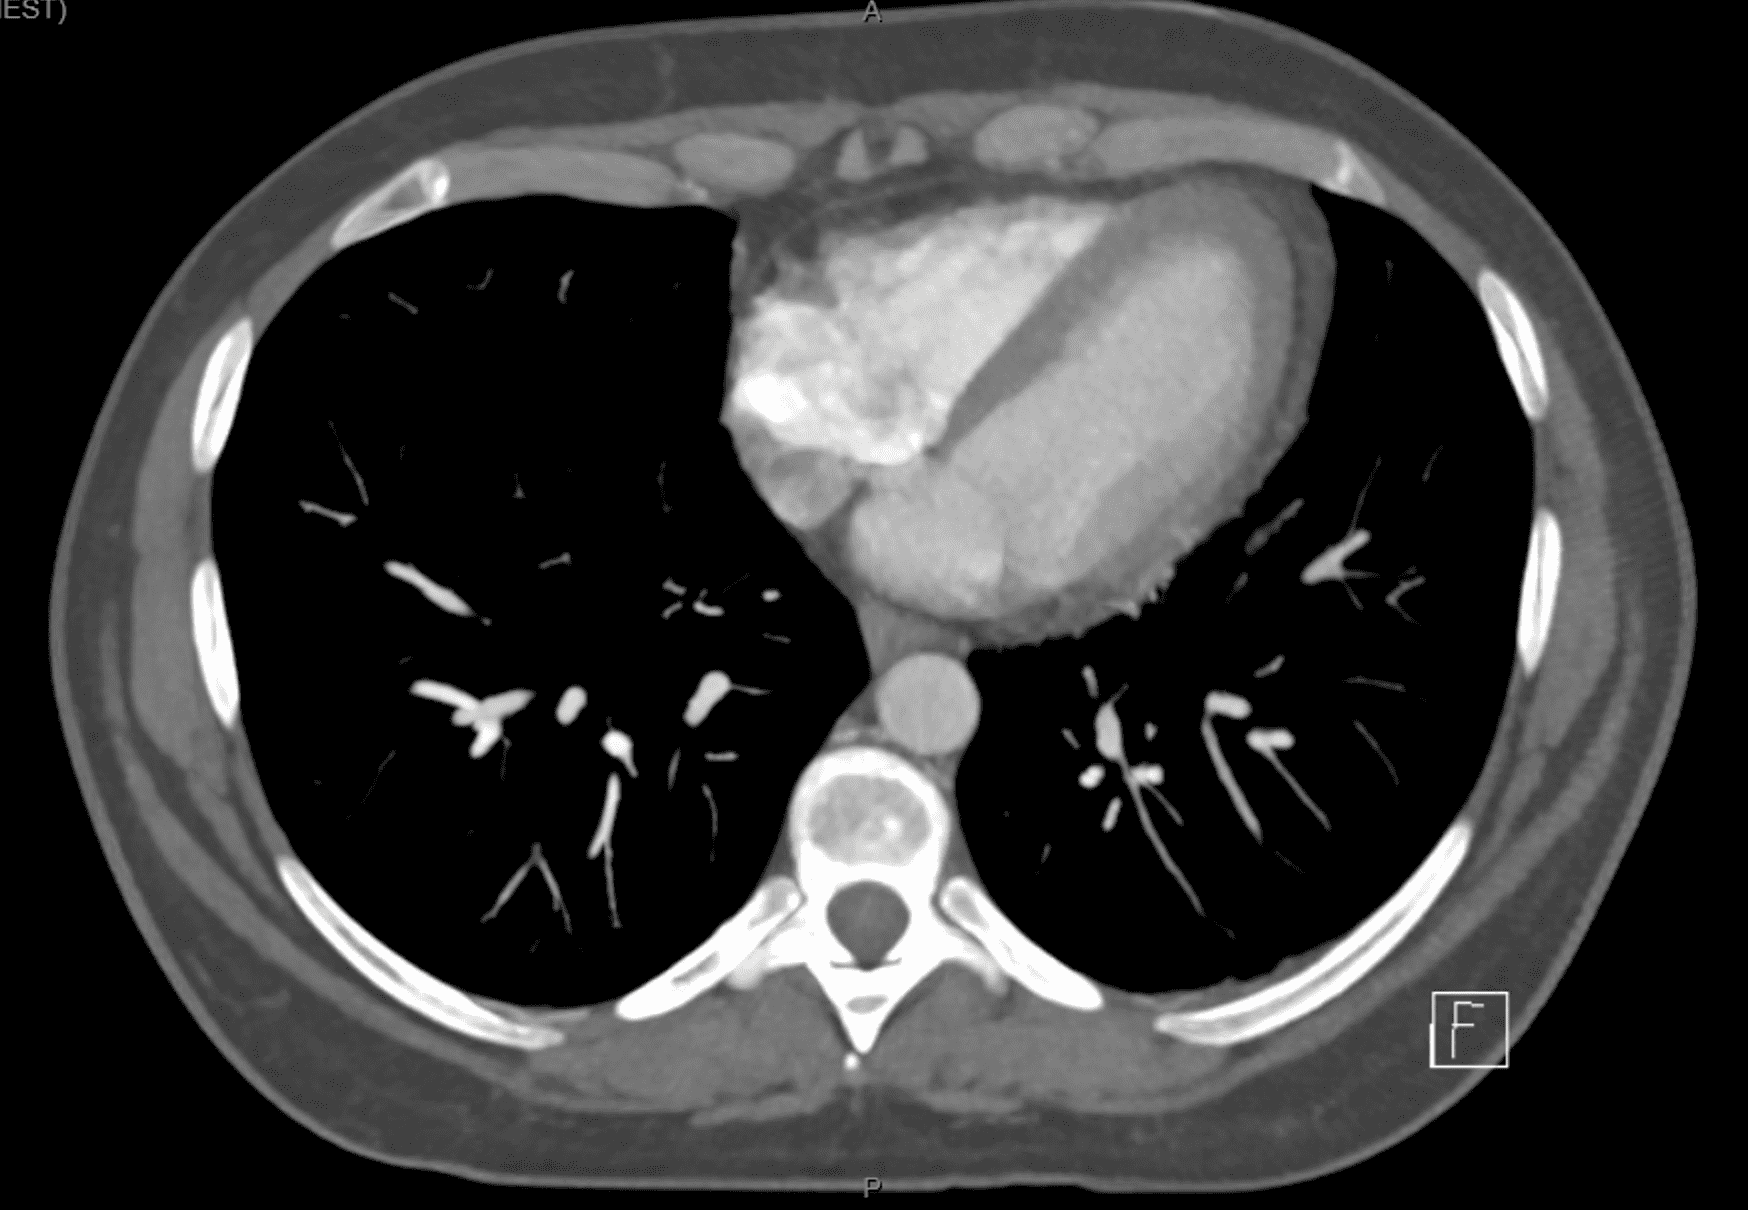

From nccommons.org

Acute epicardial fat necrosis (Radiopaedia 4232745440 Axial C+ CTPA Mayo Clinic Fat Necrosis It can occur from trauma or as a complication of surgery. Sclerosing mesenteritis (sm), an idiopathic nonneoplastic condition affecting 0.18% to 3.14% of the population, is characterized by chronic fat necrosis, inflammation, and. But liposarcoma can begin in the. Those increases plus the receiver operating characteristic curve. Fat necrosis is often triggered by an event that damages the affected tissue. Mayo Clinic Fat Necrosis.

From radiopaedia.org

Acute epicardial fat necrosis Image Mayo Clinic Fat Necrosis Fat necrosis is necrosis that occurs in parts of the body that contain a lot of fatty tissue, such as the breast. Sclerosing mesenteritis (sm), an idiopathic nonneoplastic condition affecting 0.18% to 3.14% of the population, is characterized by chronic fat necrosis, inflammation, and. Those increases plus the receiver operating characteristic curve. I know there are ways to produce more. Mayo Clinic Fat Necrosis.

Epipericardial Fat Necrosis Radiologic Diagnosis and FollowUp AJR Mayo Clinic Fat Necrosis Fat necrosis is necrosis that occurs in parts of the body that contain a lot of fatty tissue, such as the breast. Posted by rom828 @jgallagher04921, may 16 9:05am. Those increases plus the receiver operating characteristic curve. Fat necrosis is death of fat tissue due to injury and loss of blood supply. It can occur from trauma or as a. Mayo Clinic Fat Necrosis.

From www.ajronline.org

From www.jacc.org

EPICARDIAL FAT NECROSISA RARE DIFFERENTIAL DIAGNOSIS OF CHEST PAIN IN Mayo Clinic Fat Necrosis But liposarcoma can begin in the. It most often begins as a growth of cells in the belly or in the arm and leg muscles. The faee increase in the circulation parallels the increase in parent nefa released from fat necrosis. I have lumps where lymph nodes are that are sore. Fat necrosis is death of fat tissue due to. Mayo Clinic Fat Necrosis.